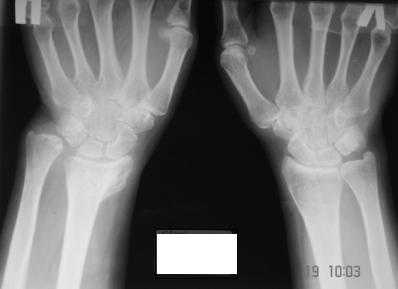

Застарелое повреждение кистевого сустава

Уважаемые коллеги! Обратилась женщина, 55 лет. Травма 3 месяца назад, лечилась по месту жительства (Рис.1). Косорукость, боли, ограничение движений.

Досняли - рис.2-6. Хотелось-бы услышать мнения об объеме операции. С уважением, Юрий Алексеевич Булахтин главный травматолог Камчатского Военно-морского госпиталя